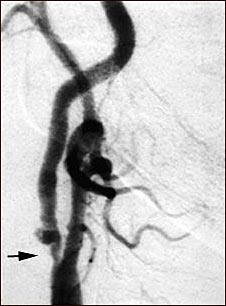

Estenosis carotídea; radiografía de la arteria derecha

Angiograma de la arteria carótida derecha que muestra un estrechamiento severo (estenosis) de la arteria carótida interna justo más allá de la bifurcación carotídea. En esta diapositiva se ve un agrandamiento de la arteria o ulceración en el área luego de la estenosis. Obsérvese el segmento estrecho cerca del extremo inferior de la imagen.